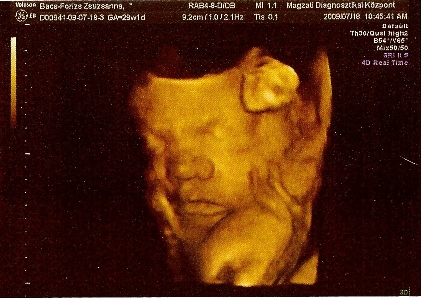

Megkérdezte, hogy hányat tettünk vissza? Én mondtam, hogy múlt héten egy volt. A férjem fogta fel a kérdést és válaszolta, hogy 3-at. Én annyira féltem, hogy nem él, hogy nem is tudtam koncentrálni. Erre Ö azt mondta, hogy itt vannak. Fel sem fogtam, nem akartam elhinni. A férjemet figyeltem, aki egyre sápadtabb volt. Kérdeztem, hogy mind a három? Élnek? A 17x17mm-es petezsákomban 5,2mm CTL méretű baba van szuper erős szívhanggal, annyira jó volt hallgatni, azóta is csak arra tudok gondolni. A 15x15mm-es petezsákban még csak lüktetős szívecske van, de ott is szép szikhólyag mint az előzőnél, és van még egy 9x9mm-es petezsákom, amiben baba még nem látszik, de azt mondta V.-doki, hogy ő sokáig vándorolt és csak nemrég ágyazódott be, jövő keddre kiderül, hogy mi van vele.

Próbálok feltenni képet, bár csak a mobilommal tudom itt a balcsin lefotózni az uhus képet, így nem lesz jó minőség.